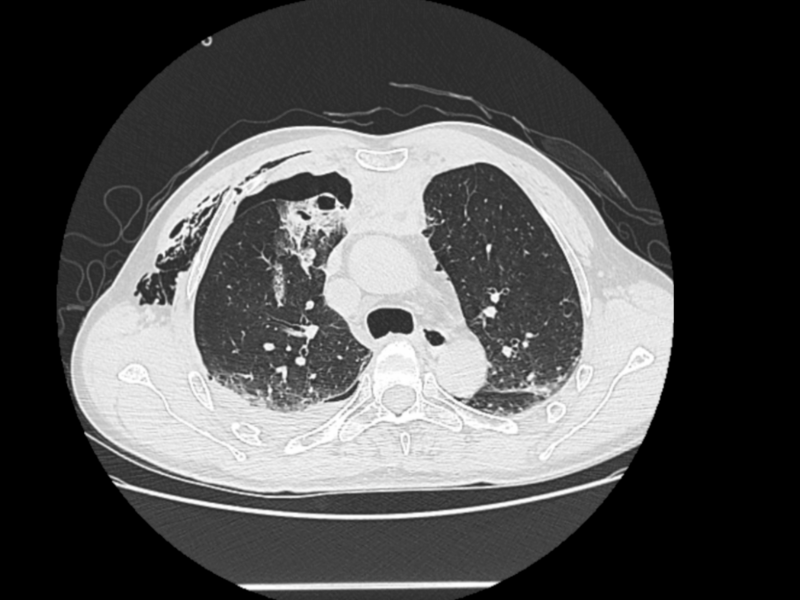

2025年3月7日,對于薛先生來說,是人生的至暗時刻。在工作時,三米高空的重物轟然墜落,將他重重砸倒。當(dāng)急救車呼嘯著沖進(jìn)醫(yī)院時,薛先生已面色蒼白,呼吸急促艱難,每一次喘息都伴隨著痛苦的呻吟,醫(yī)護(hù)人員迅速為薛先生完善身體全面檢查。檢查結(jié)果顯示,薛先生傷情復(fù)雜,其右側(cè)第1-11肋及左側(cè)第1-3、6肋骨折,共有15條肋骨20余處骨折,雙側(cè)創(chuàng)傷性血氣胸、胸腔積液,肺挫傷并破裂,胸骨、胸椎、肩胛骨多處骨折,此外還有臟器損傷等一系列復(fù)雜病癥。這一連串的診斷,仿佛給薛先生的生命套上了層層枷鎖。

△治療前